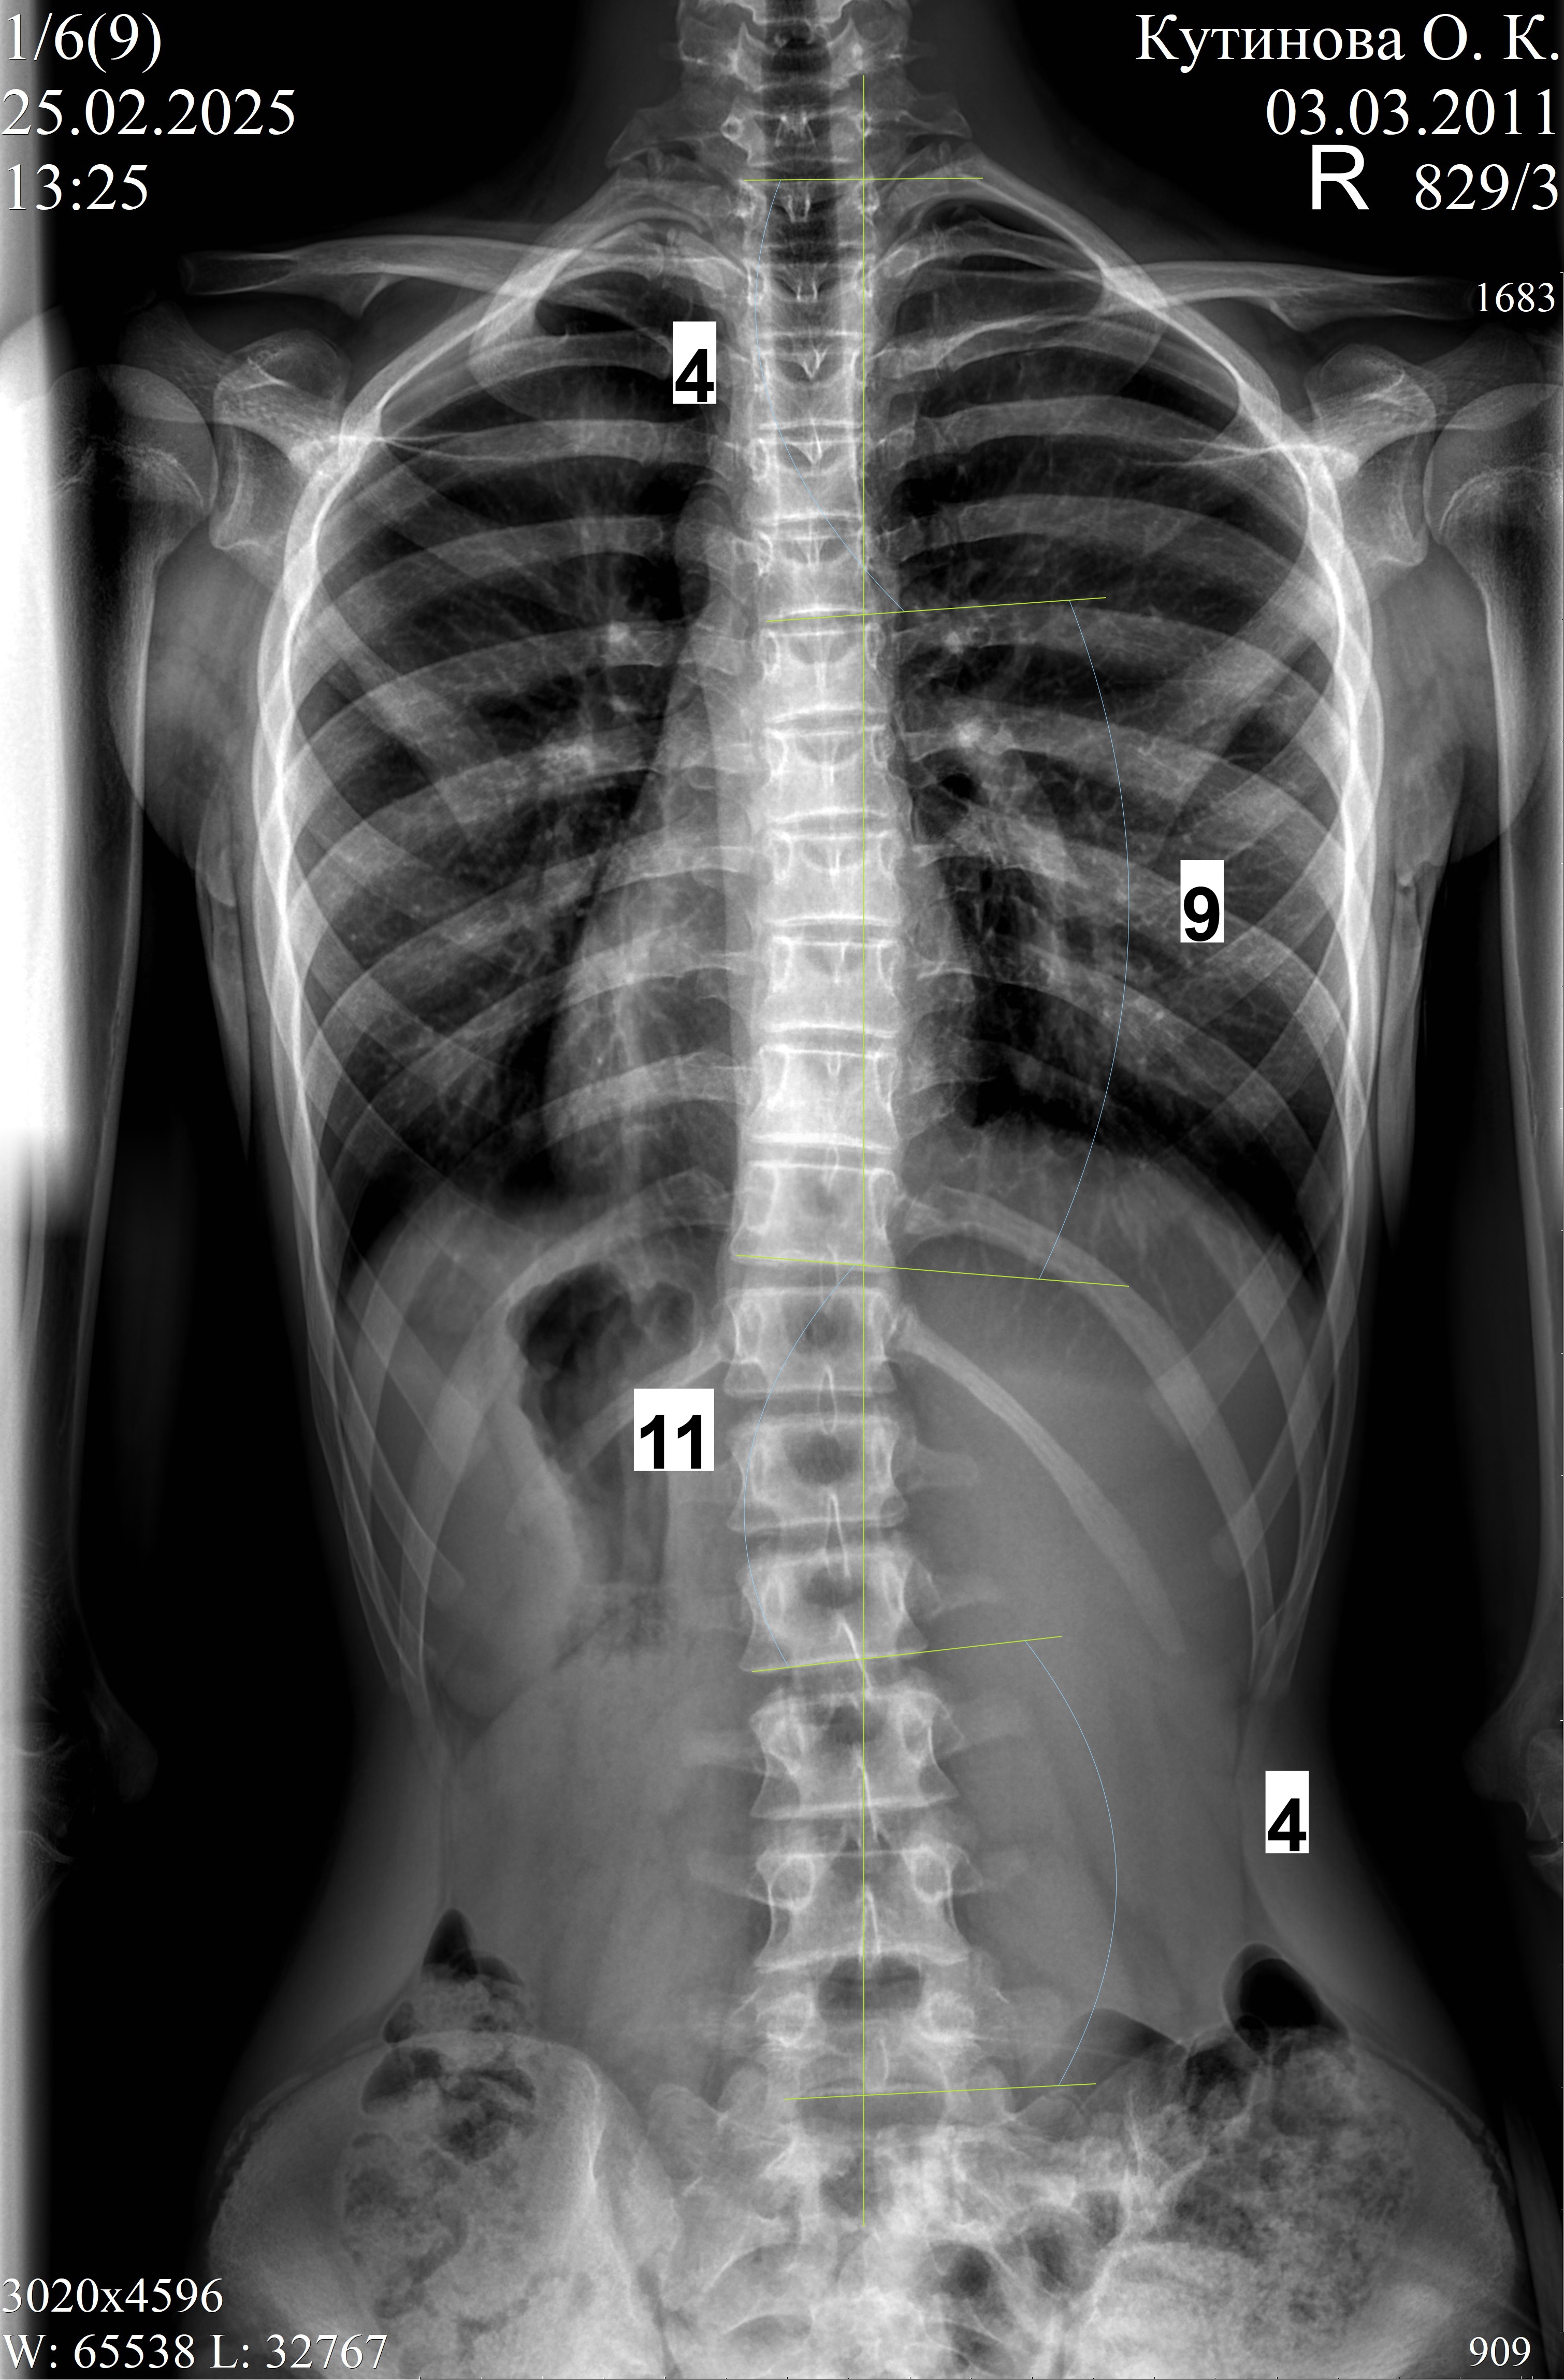

В декабре 2024 (6,5 лет в корсете, взраст 13 лет 9 мес) нам сказали что делать новый все таки не будут, градусы маленькие, вдруг гиперкоррекция случится) очень было тревожно, но корсет сняли, через три месяца рентген-осмотр 25.02.2025 - пока все ок, еще три месяца гуляем без корсета. Будем делать рентген каждые три месяца, так сейчас самый опасный момент - М нет, рост идет, за три месяца добавила 1 см, итого 177,5 см, через 5 дней 14 лет.

Обновление от мая 2025, рост 179,5(+2см за 3 мес)

Без корсета 6 мес. По снимкам даже улучшение, если это не погрешность, то я в шоке.